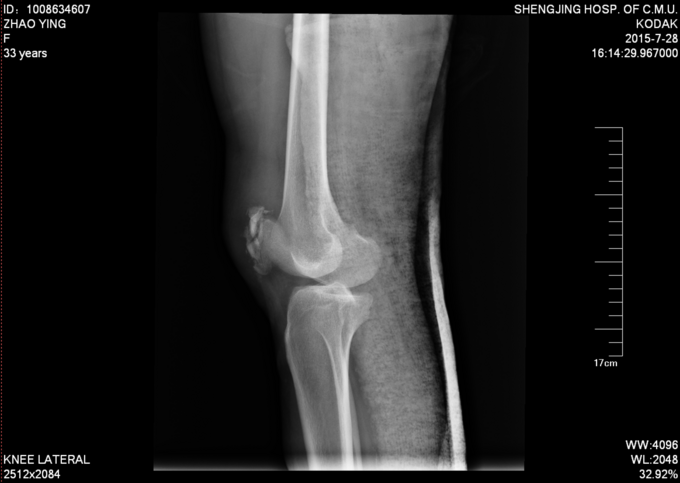

现病史:患者家属代诉于2015年7月23日5点发生车祸,车祸后致右膝部疼痛肿胀活动受限,当时无意识不清,120送至当地医院(辽中县医院),后为进一步治疗,急诊就诊于中国医科大学附属盛京医院,行X线片检查示:右髌骨开放性骨折,急诊给予清创缝合,观察患者病情稳定后,急诊以“右髌骨开放性骨折”为诊断收住我科·。伤来患者无头痛及发热,无咳嗽咳痰,无腹痛及恶心呕吐,饮食睡眠可,大小便正常。

右膝关节已清创缝合,缝合处约10cm不规则创口,右髌骨处软组织肿胀,右膝关节活动受限,右下肢皮肤感觉可,右下肢活动可,。右下肢足背动脉搏动良好,末梢血运良好,皮温正常。

右髌骨开放性骨折 患者急诊行清创缝合后,入院检查后,患者病情平稳,创口1至2天定期换药,观察患者创口愈合,患肢抬高,给予消炎消肿等对症治疗后。入院约一周后创口处无红肿,无渗出,全麻下行右髌骨开放性骨折切口复位张力带内固定术。